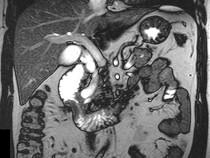

问题 男,43岁,上腹胀痛2个月,频繁呕吐,呕吐物为黄绿色,影像所见如图,可能的诊断为()

选项 A.十二指肠溃疡 B.十二指肠结核 C.十二指肠中分化腺癌 D.十二指肠克罗恩病 E.十二指肠淋巴瘤

答案 C